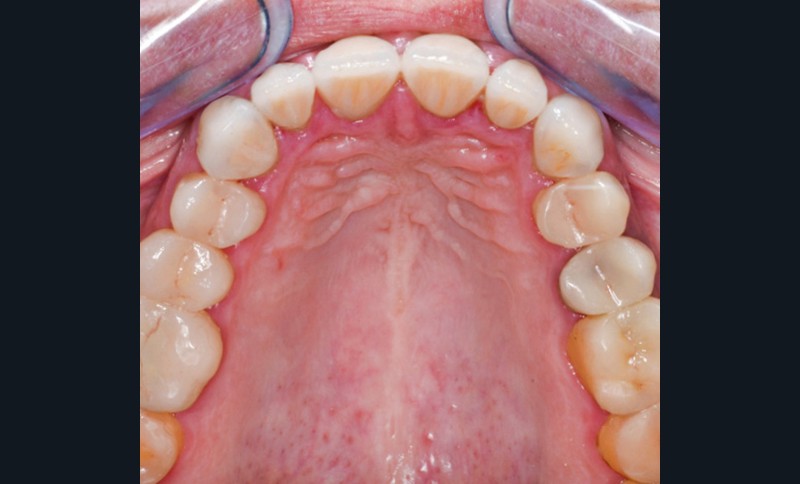

Mme V. est adressée au cabinet dentaire pour une réhabilitation de son sourire. À l’examen clinique, elle présente des usures sur l’ensemble de son maxillaire (fig. 17 et 18). Après évaluation du décalage OIM-ORC, une position de référence en relation centrée avec une dimension verticale augmentée est enregistrée. Pour valider cette position, il est demandé au laboratoire de réaliser un wax-up virtuel. Ce dernier est validé puis transféré en bouche pour essayage (fig. 19 et 20).